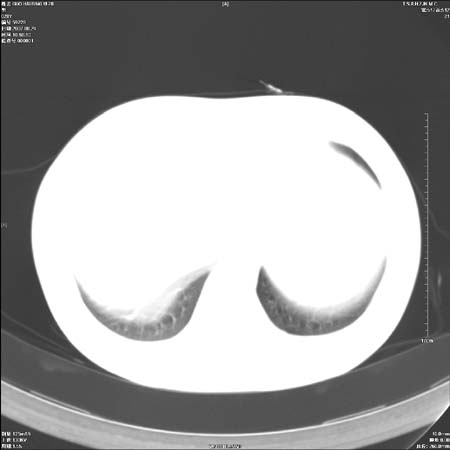

男性,28岁,体检发现左肺病变,患者只有背部隐痛感,哀哉,真不忍心下诊断啊。

左肺门区软组织肿块,左肺上叶支气管开口消失,纵隔内见肿大淋巴结,考虑左中心型肺部,可以做纤支镜取病理确认.

左侧肺癌纵隔淋巴结转移。太年轻了,可惜。。。。。。。

左肺肺门区肿块影,分叶明显:诊断肺癌应该没有疑问。

左肺肺门区肿块影,分叶明显,左肺上叶支气管开口受压,纵隔内见肿大淋巴结,考虑左中心型肺癌。

支持左上叶中央型肺癌伴纵隔淋巴结转移.

左上叶中央型肺癌伴纵隔淋巴结转移

左侧肺门区见一块状病灶可见分叶,纵隔内及左肺门见肿大淋巴结,应该是周围型肺癌而不是中心型肺癌,原因有以下2点,1未见阻塞肺气肿和阻塞性炎症,这么大肿块如果是中心型肺癌就是未分化型或小细胞型肺癌不出现阻塞性肺不张也应该有阻塞炎症或阻塞性肺气肿,2如果是中心型肺癌临床出现最早的症状是咳嗽(此时可无任何异常影象),而此人这么大肿块只有背部隐痛是体检才发现无法解释.

左肺中心型肺癌并纵隔淋巴结转移!考虑为小细胞肺癌,没有手术机会了,只能进行放化了,疗效不错,但极易复发。没办法,现在肿瘤年轻化越来越明显了。